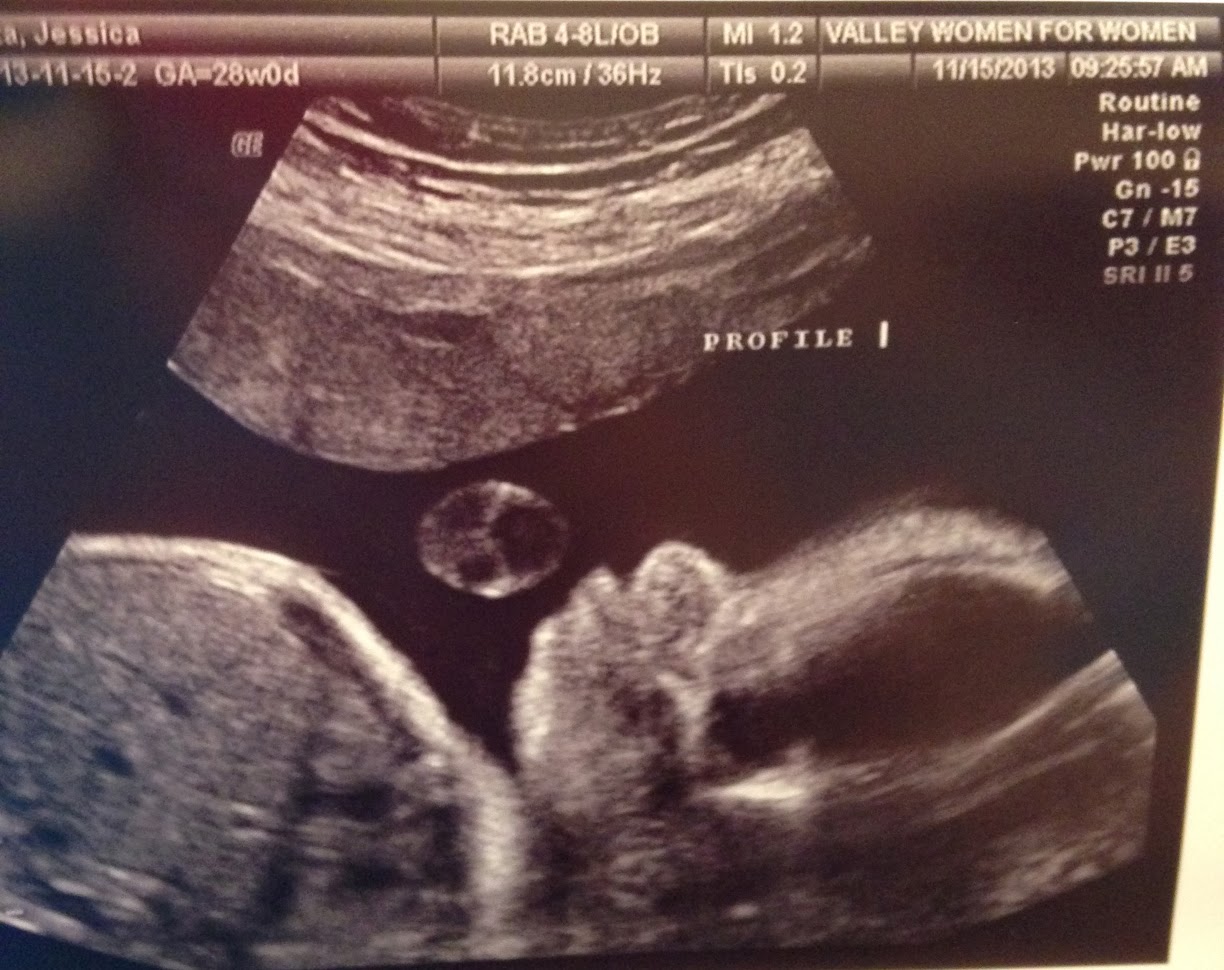

The great thing about this challenge-laden appointment is the ultrasound. I’m still amazed at what technology allows us to see and hear in there. This week, our baby boy is measuring about a week ahead of schedule at 3lbs 2oz. After 14 weeks, all babies grow at their own pace so this doesn’t mean he will come out a week early, although I wouldn’t protest.

Drew and I got to see his brain, his spine, the bones in his legs, and other indicators of his growth that all show he’s a healthy baby. He’s in the correct position for labor, so we hope he stays that way for the next three months.